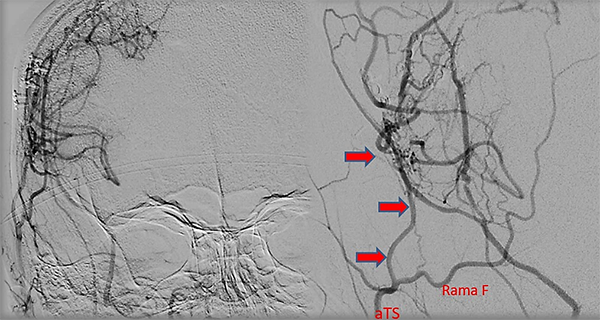

Caso clínico #1: PR masculino de 20 años sin antecedentes clínicos, estudiado por cefaleas de varios meses de evolución. La RMN no presenta lesiones y la ARM evidencia una disminución del flujo de la arteria cerebral media derecha. La ADC muestra la estenosis progresiva de la arteria carótida interna derecha supraclinoidea, ausencia de opacificación del origen de la arteria cerebral media y anterior, presencia de vasos de MM con escasa circulación colateral desde carótida interna izquierda a través de la comunicante anterior; corresponde a un grado 3 de Suzuki (Fig. 1). Se realizó una revascularización cerebral combinada: un bpTS más EDMS derecho, la evolución postoperatoria fue sin complicaciones y la ADC diferida muestra una buena perfusión cerebral a través del bypass y la sinangiosis (Fig. 2). El control clínico a 4 años es favorable y las imágenes de RMN y RMA evidencian ausencia de nuevas lesiones isquémicas y adecuada revascularización.

Fig. 1 Caso clínico #1. ARM y ADC preoperatoria, obsérvese la estenosis progresiva de la arteria carótida supraclinoidea derecha con ausencia del origen de las arterias cerebral anterior y media. Corresponde a un grado 3 de Suzuki